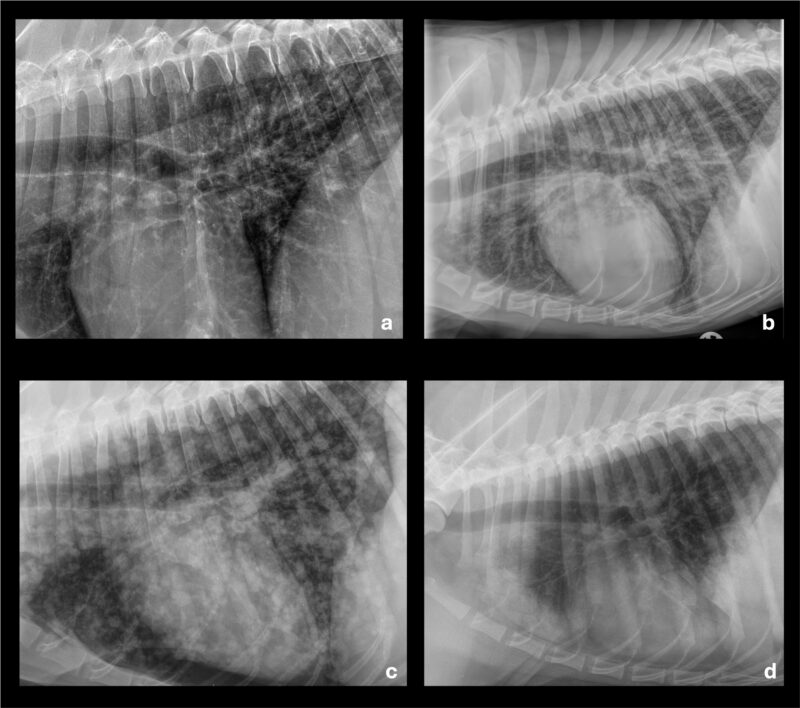

Radiologische Lungenmuster (Abb. 1) dienen der strukturierten Beschreibung, sind jedoch keine Diagnosen. Ein alveoläres Muster mit Aerobronchogrammen findet sich typischerweise bei Pneumonie, Lungenödem oder Atelektase, wobei die Verteilung (kranioventral vs. perihilär/kaudodorsal) wichtige Hinweise auf die Ätiologie liefert. Das interstitielle Muster ist besonders unspezifisch und kann frühe entzündliche Prozesse, Ödeme, Blutungen, Neoplasien oder fibrotische Veränderungen widerspiegeln. Ein bronchiales Muster findet sich häufig bei (chronischen) Atemwegserkrankungen, während ein noduläres Muster differenzialdiagnostisch Neoplasien, granulomatöse Prozesse oder Abszesse umfasst. Zentrale Limitation des Röntgens ist die Überlagerung anatomischer Strukturen, wodurch kleine Läsionen, frühe Parenchymveränderungen oder komplexe Atemwegserkrankungen häufig nicht sicher erfasst werden. In diesen Fällen ist eine weiterführende Schnittbilddiagnostik indiziert.

In Tabelle 1 sind die verschiedenen Röntgenmuster mit ihren Merkmalen, relevanten Differentialdiagnosen und den typischen Limitationen gelistet.